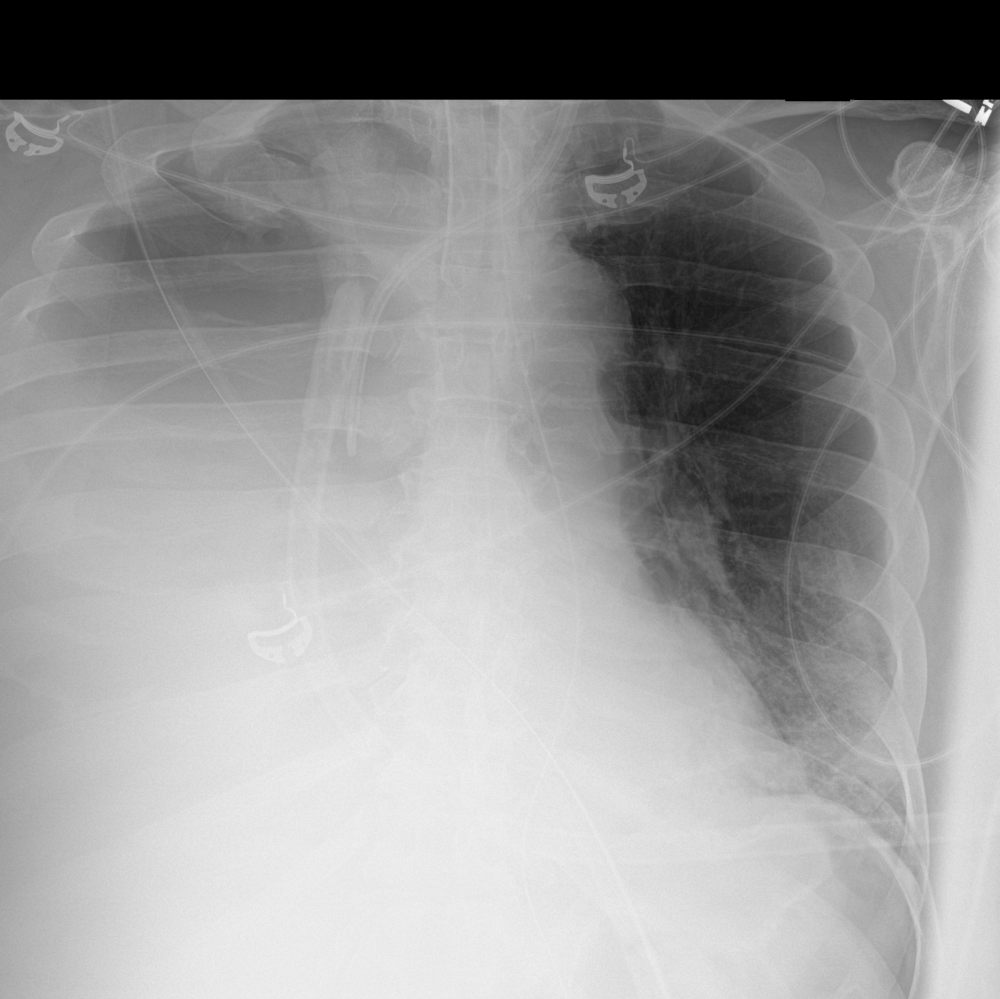

A 54-year-old male with respiratory difficulty.

Results

ChestView detected an infectious region in the right lower lobe and incidentally identified left hilar lymphadenopathy